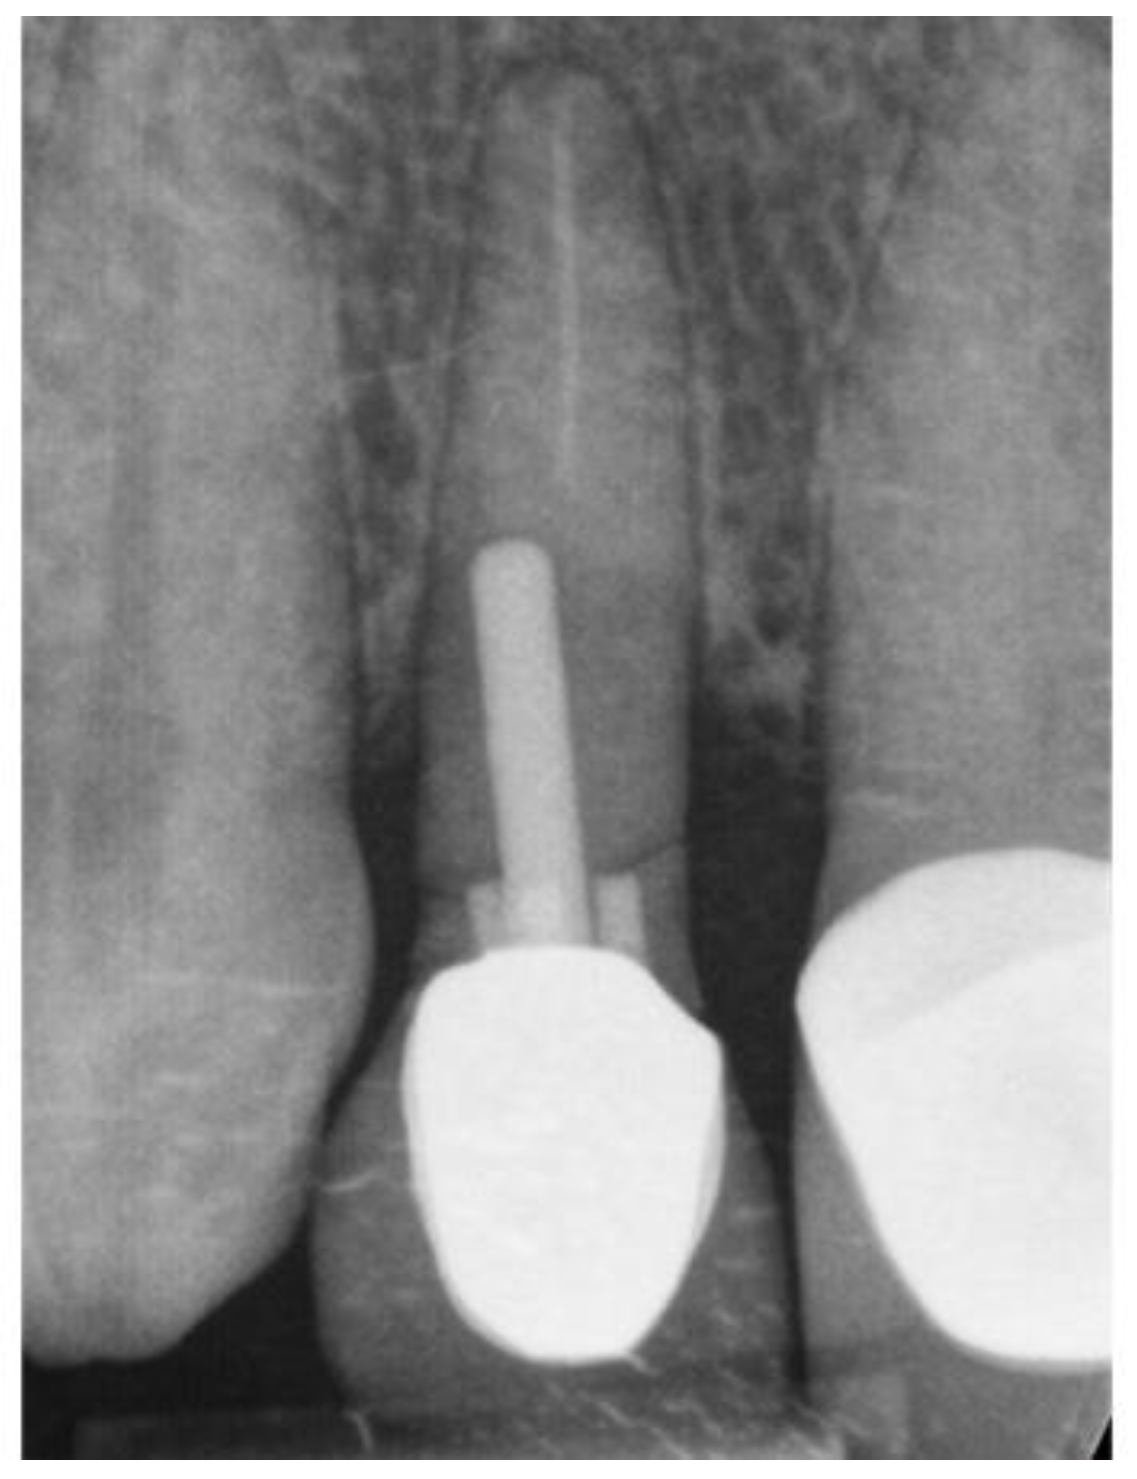

2.4. Radiological Evaluation

Labial plate dimension

Presence and width of the labial plate was measured prior to immediate tooth replacement therapy and at least 12 months (range 12-20 months) afterwards. Measurements were taken (in millimetres) at one level: the implant-abutment interface (IAI) equivalent to the midfacial labial plate bone crest [24,25] At this level, two reference points were defined. (1) the outermost aspect of the labial bone plate, and (2) the first radiographic bone-to-implant contact point connected by a straight line perpendicular to the implant body. The distance between the two points was measured using proprietary CBCT digital imaging software.

Figure 10. 11 & 12. CNCT sections immediate pre op, immediate post op and 12 months loading.

Preprints 86078 g009

3.1. Radiographic Evaluation

Thirty-one sets of CBCTS taken at the time of ITRT and at least twelve months after loading were available for radiographic evaluation. The mean LBT at time of ITRT was 0.7mm with a range from 0mm to 2.1mm. At follow up of at least 12 months of implant loading, the mean LBT was 2.3mm, with a range of 0.8mm to 4.3mm. This represents a mean increase in LBT of 1.7mm.

Figure 18. Pre-op radiograph.

Preprints 86078 g015